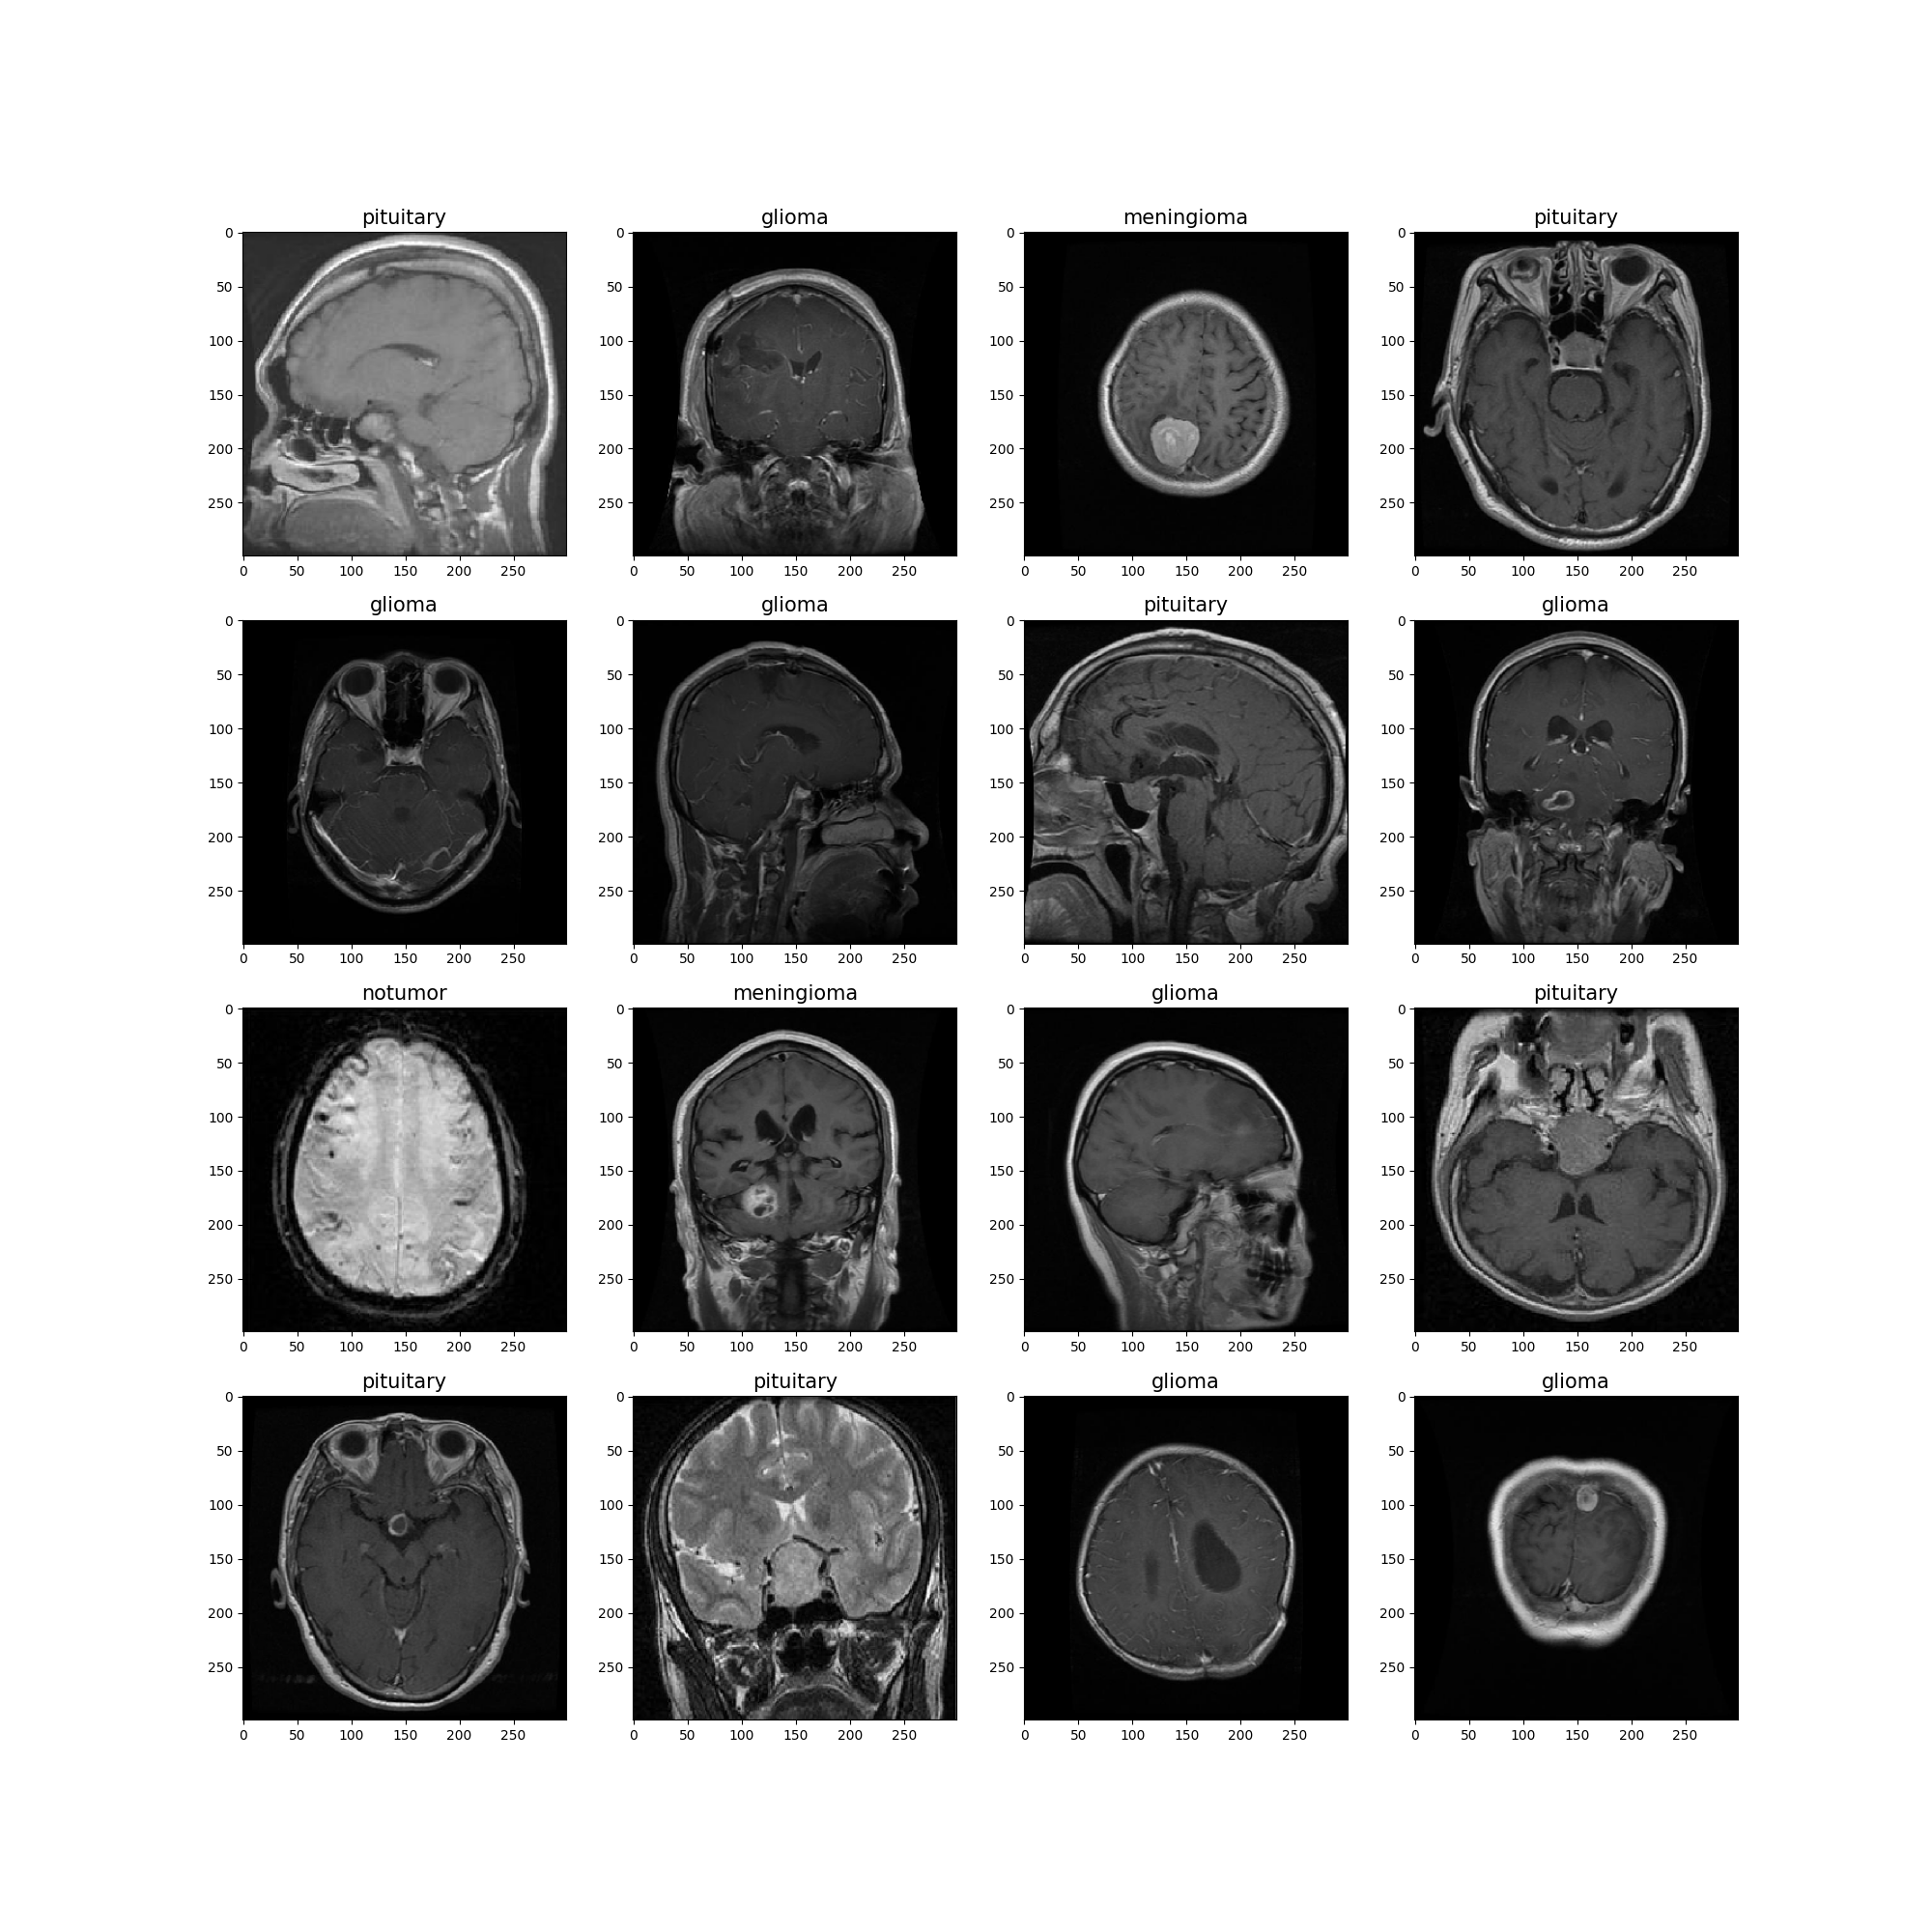

Sample Predictions

This model is a fine-tuned Xception network for classifying brain MRI scans into 4 categories:

glioma, meningioma, notumor, pituitary.

- Classes: 4 (glioma, meningioma, notumor, pituitary)